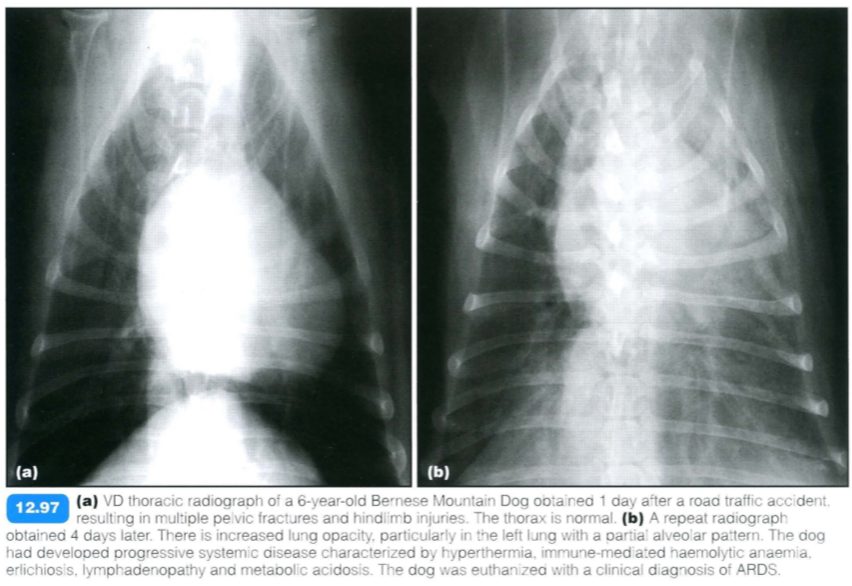

Acute Respiratory Distress Syndrome

(ARDS)

ARDS is a human term defined as acute fulminating respiratory failure, resulting from a variety of diseases , leading to diffuse lung injury. It may also be called adult respiratory distress syndrome or shock lung.

ARDS is considered to be a subgroup of non- cardiogenic oedema. It is part of the systemic inflammatory response, leading to increased vascular permeability, pulmonary hypertension and airway constriction and obstruction.

ARDS is possibly more common in younger dogs; no sex predisposition has been reported. A familial form is suspected in young Dalmatians (< 1 year old), some of which also have renal aplasia or hydrocephalus.

Radiographic findings include: